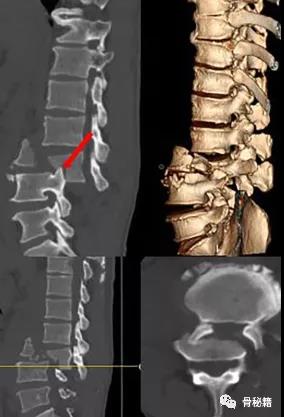

高能量损伤造成的脊柱骨折前后脱位是脊柱骨折复位的难点和要点

前后移位

对于前后移位就相对复杂一些1、解锁脊柱的关节面

如果坎墩严重,需要先植入椎弓根螺钉,咬除部分后方椎板,进行后柱的撑开。